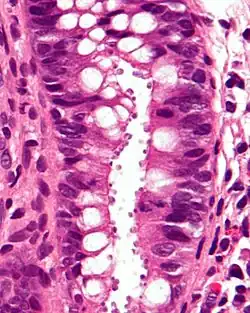

| Micrograph showing cryptosporidiosis. The cryptosporidium are the small, round bodies in apical vacuoles on the surface of the epithelium. H&E stain. Colonic biopsy. | |

Other staining techniques include acid-fast staining,[28] which will stain the oocysts red.[27] One type of acid-fast stain is the Kinyoun stain.[23] Giemsa staining can also be performed.[24] Part of the small intestine can be stained with hematoxylin and eosin (H & E), which will show oocysts attached to the epithelial cells.[27]